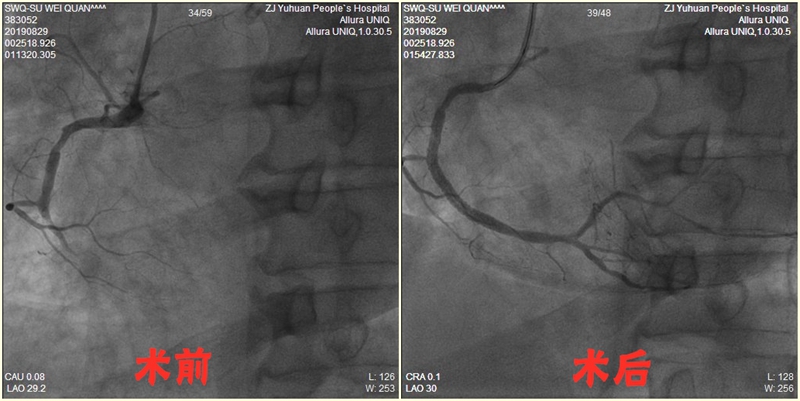

1.经皮冠状动脉介入治疗(PCI )

在玉环市内率先开展经皮冠状动脉介入诊疗技术及急性心梗的急诊介入治疗,最短 D to W 时间 仅16分钟,最高年龄96岁。冠脉介入及心梗急诊介入技术获玉环市第二届医学学科“科技创新奖”新技术组一等奖。